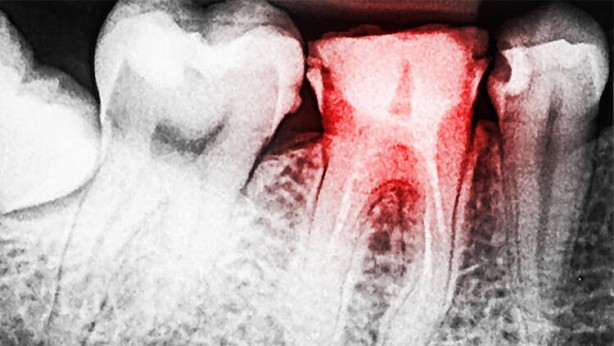

6-10 ay arasında diş hekimlerine kontrole gidin.

Diş fırçasını su ile ıslatmadan kullanın. Çünkü su, diş macunundaki flor oranını düşürüyor.

Unutulmamalıdır ki çürük erken aşamada tespit edilirse geri döndürülebilir.